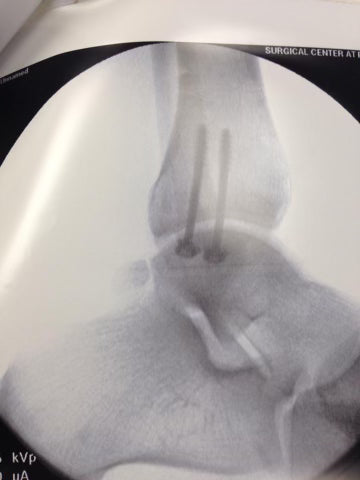

Suddenly, I couldn’t steer anymore and I couldn't land. The force of the snow catapulted me downwards about 30 feet and I landed hard onto a tree immediately breaking my tibia, fibula and medial malleolus bone from the impact. The size of the avalanche was not enough to bury me, but threw me into an uncontrollable wash out in the trees.

HB: Hold up—what is the medial malleolus and how did you know you broke your bones?

JC: That’s the circular bone that is inside of your ankle, and that played a particularly spicy role in this story. And I just felt it break instantly haha.

JC: Yeah, a couple rips of morphine later I was fine haha. But the nurse brought me extra jell-o and was extra apologetic because I was right—it was super broken now. Two surgeries and ten years later, I still have the hardware in my ankle. It straight up looks like screws you’d get from Home Depot, but it did the job.